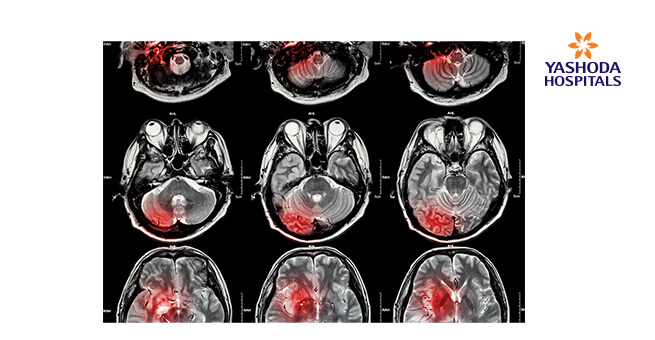

- మాగ్నెటిక్ రిసోనెన్స్ ఇమేజింగ్ (MRI): ఇస్కీమిక్ స్ట్రోక్ మరియు మెదడు రక్తస్రావం వల్ల దెబ్బతిన్న కణజాలాలను గుర్తించడానికి ఎంఆర్ఐ చేయవచ్చు. ధమనులు మరియు సిరలను స్పష్టంగా వీక్షించడానికి మరియు రక్త ప్రవాహాన్ని హైలైట్ చేయడానికి, వైద్యులు మాగ్నెటిక్ రిసోనెన్స్ ఆంగియోగ్రఫీ లేదా మాగ్నెటిక్ రిసోనెన్స్ వెనోగ్రఫీ అని పిలువబడే ప్రక్రియలో డై(dye)ని ఇంజెక్ట్ చేయాల్సి ఉంటుంది.